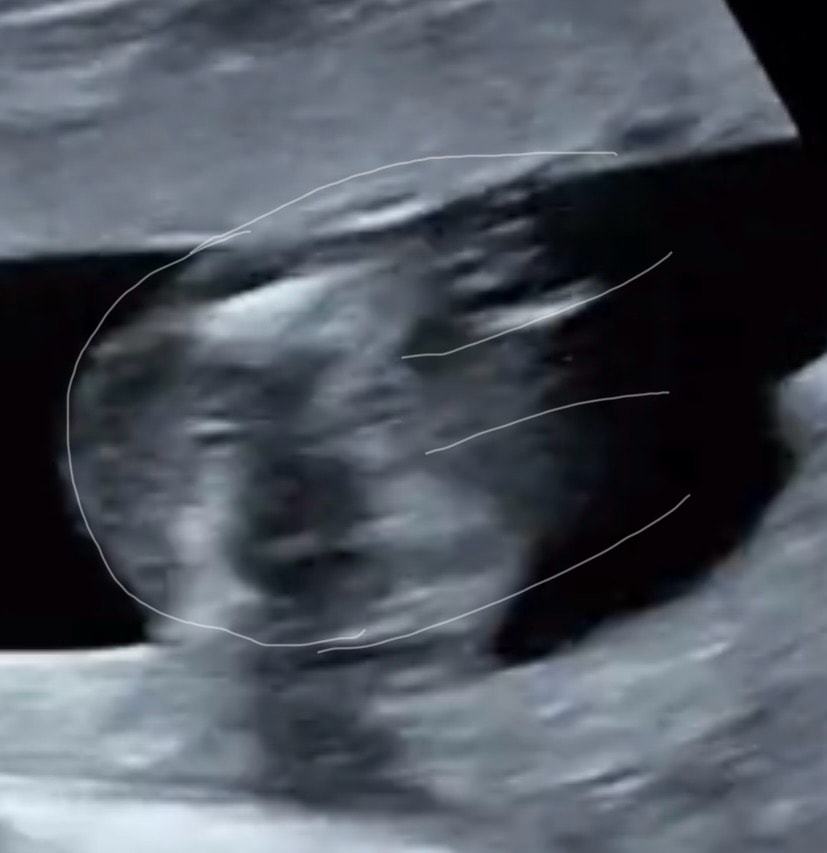

❆Elena❆, да я уверена была, сын. Уже и кое что ему купила… теперь в мае спрошу. Изображение Вот наверху дочка моя, внизу сейчас. Изображение А еще вот. Девочки мне сказали губы и клитор торчит

Алина, ну как бы да, это не похож на писюн! Дай бог вам здоровую девочку!!